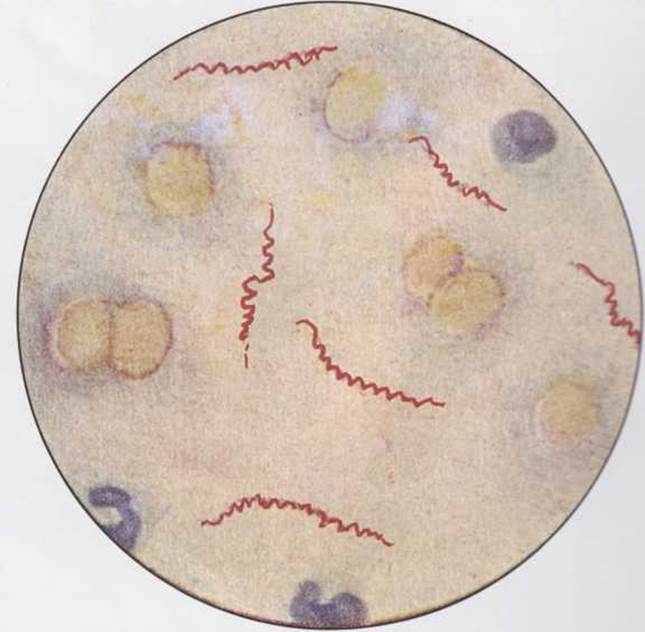

Лептоспиры: фотографии удивительных микроорганизмов

:max_bytes(150000):strip_icc()/spirillum_updated-5be08db6c9e77c002697c64a.jpg)